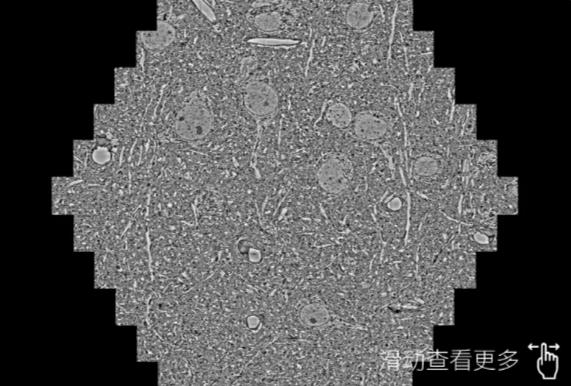

鼠脑切片。左图使用阜阳蔡司阜阳扫描电镜MultiSEM706对165μmx143pm面积区域成像,耗时仅需1.5秒。右图为鼠脑切片中30μm区域放大效果。样品由芝加哥大学B.Kasthuri提供。

使用蔡司高速阜阳扫描电镜MultiSEM对1mm²人脑皮层组织进行高分辨成像,并对其中的各种细胞结构进行三维重构分析。左图展示了2x3mm²组织平面中锥体神经元的三维重构效果。右图显示了局部体积神经元三维重构。图像由哈佛大学chtman实验室提供,渲染图由D. Berger 制作。